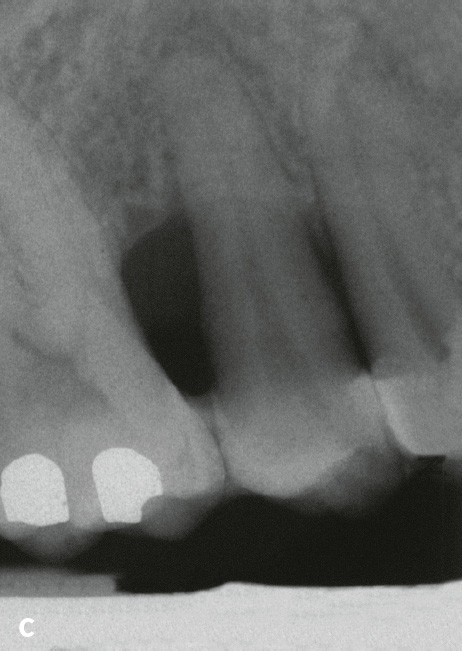

Auch die Geschwindigkeit, mit der eine Läsion voranschreitet, kann Hinweise auf die Genese geben: Parodontitis ist eine chronische Erkrankung mit zumeist langwierigem Verlauf. Entsteht isoliert an einer Stelle innerhalb von nur 2 Jahren ein Knocheneinbruch, der bis ins apikale Wurzeldrittel reicht, sind eine primär endodontale Genese oder eine vertikale Wurzelfraktur sehr wahrscheinlich (Tab. 2). Ein weiteres Unterscheidungskriterium kann die Form der knöchernen Läsionen sein: Nach koronal weite und sich nach apikal v-förmig verengende Defekte weisen auf Läsionen primär parodontalen Ursprungs hin, während runde und halbrunde Querschnitte, bei denen sich der Knochen nach koronal wieder verengt, eher auf primär endodontale Läsionen hinweisen (Tab. 2, Abb. 10). Die knöcherne Läsion hat dort ihren größten Durchmesser, wo sie ihren Ausgang nahm.

Abb. 10 Der endodontal verursachte Entzündungsprozess zerstört die Verbindung zwischen den im Knochen und im Wurzelzement verankerten Desmodontalfasern. Der proximale Anteil dieser Fasern bleibt aber anscheinend zumindest anfangs intakt (Abb. 5), sodass sich nach Eliminierung der endodontalen Entzündungsursache durch Wurzelkanalbehandlung die Kontinuität der Desmodontalfasern wiederherstellen kann. Röntgenaufnahmen von Zahn 22, der bei Erstbefundung asensibel auf Kältetest reagierte: August 1997: Masterpoint-Röntgenaufnahme: Distal erstreckt sich eine knöcherne Läsion vom Limbus alveolaris bis zum Apex. Die knöcherne Läsion hat ihre größte Ausdehnung im apikalen Wurzeldrittel; September 2000: nahezu vollständige Auffüllung des Knochendefekts nach Desinfektion und Füllung des Wurzelkanals.